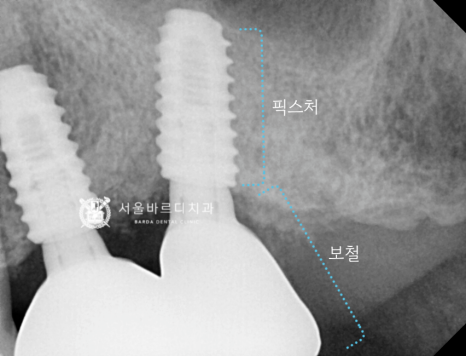

임플란트의 뿌리 역할을 하는

픽스처를 넣기 위해서 충분한 폭이 필요한데

이를 뽑은지 오래되어 치조골의 폭이

많이 좁아져 있었습니다.

가이드 장치를 끼운 상태에서

해당 부위만 길을 만들어서 픽스처를 심은 덕분에

하치조 신경관의 손상 없이 바르게 심겼네요.